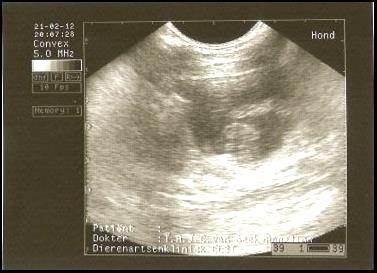

ER IS NIEUWS! Wisper is gedekt door haar liefde Bikkel (Boef) op 21/22 januari. We hopen in de lente 2012 de pups van het mooie paar te verwelkomen! Op 21 februari is er een echo gemaakt en ja hoor….. WISPER IS DRACHTIG! |